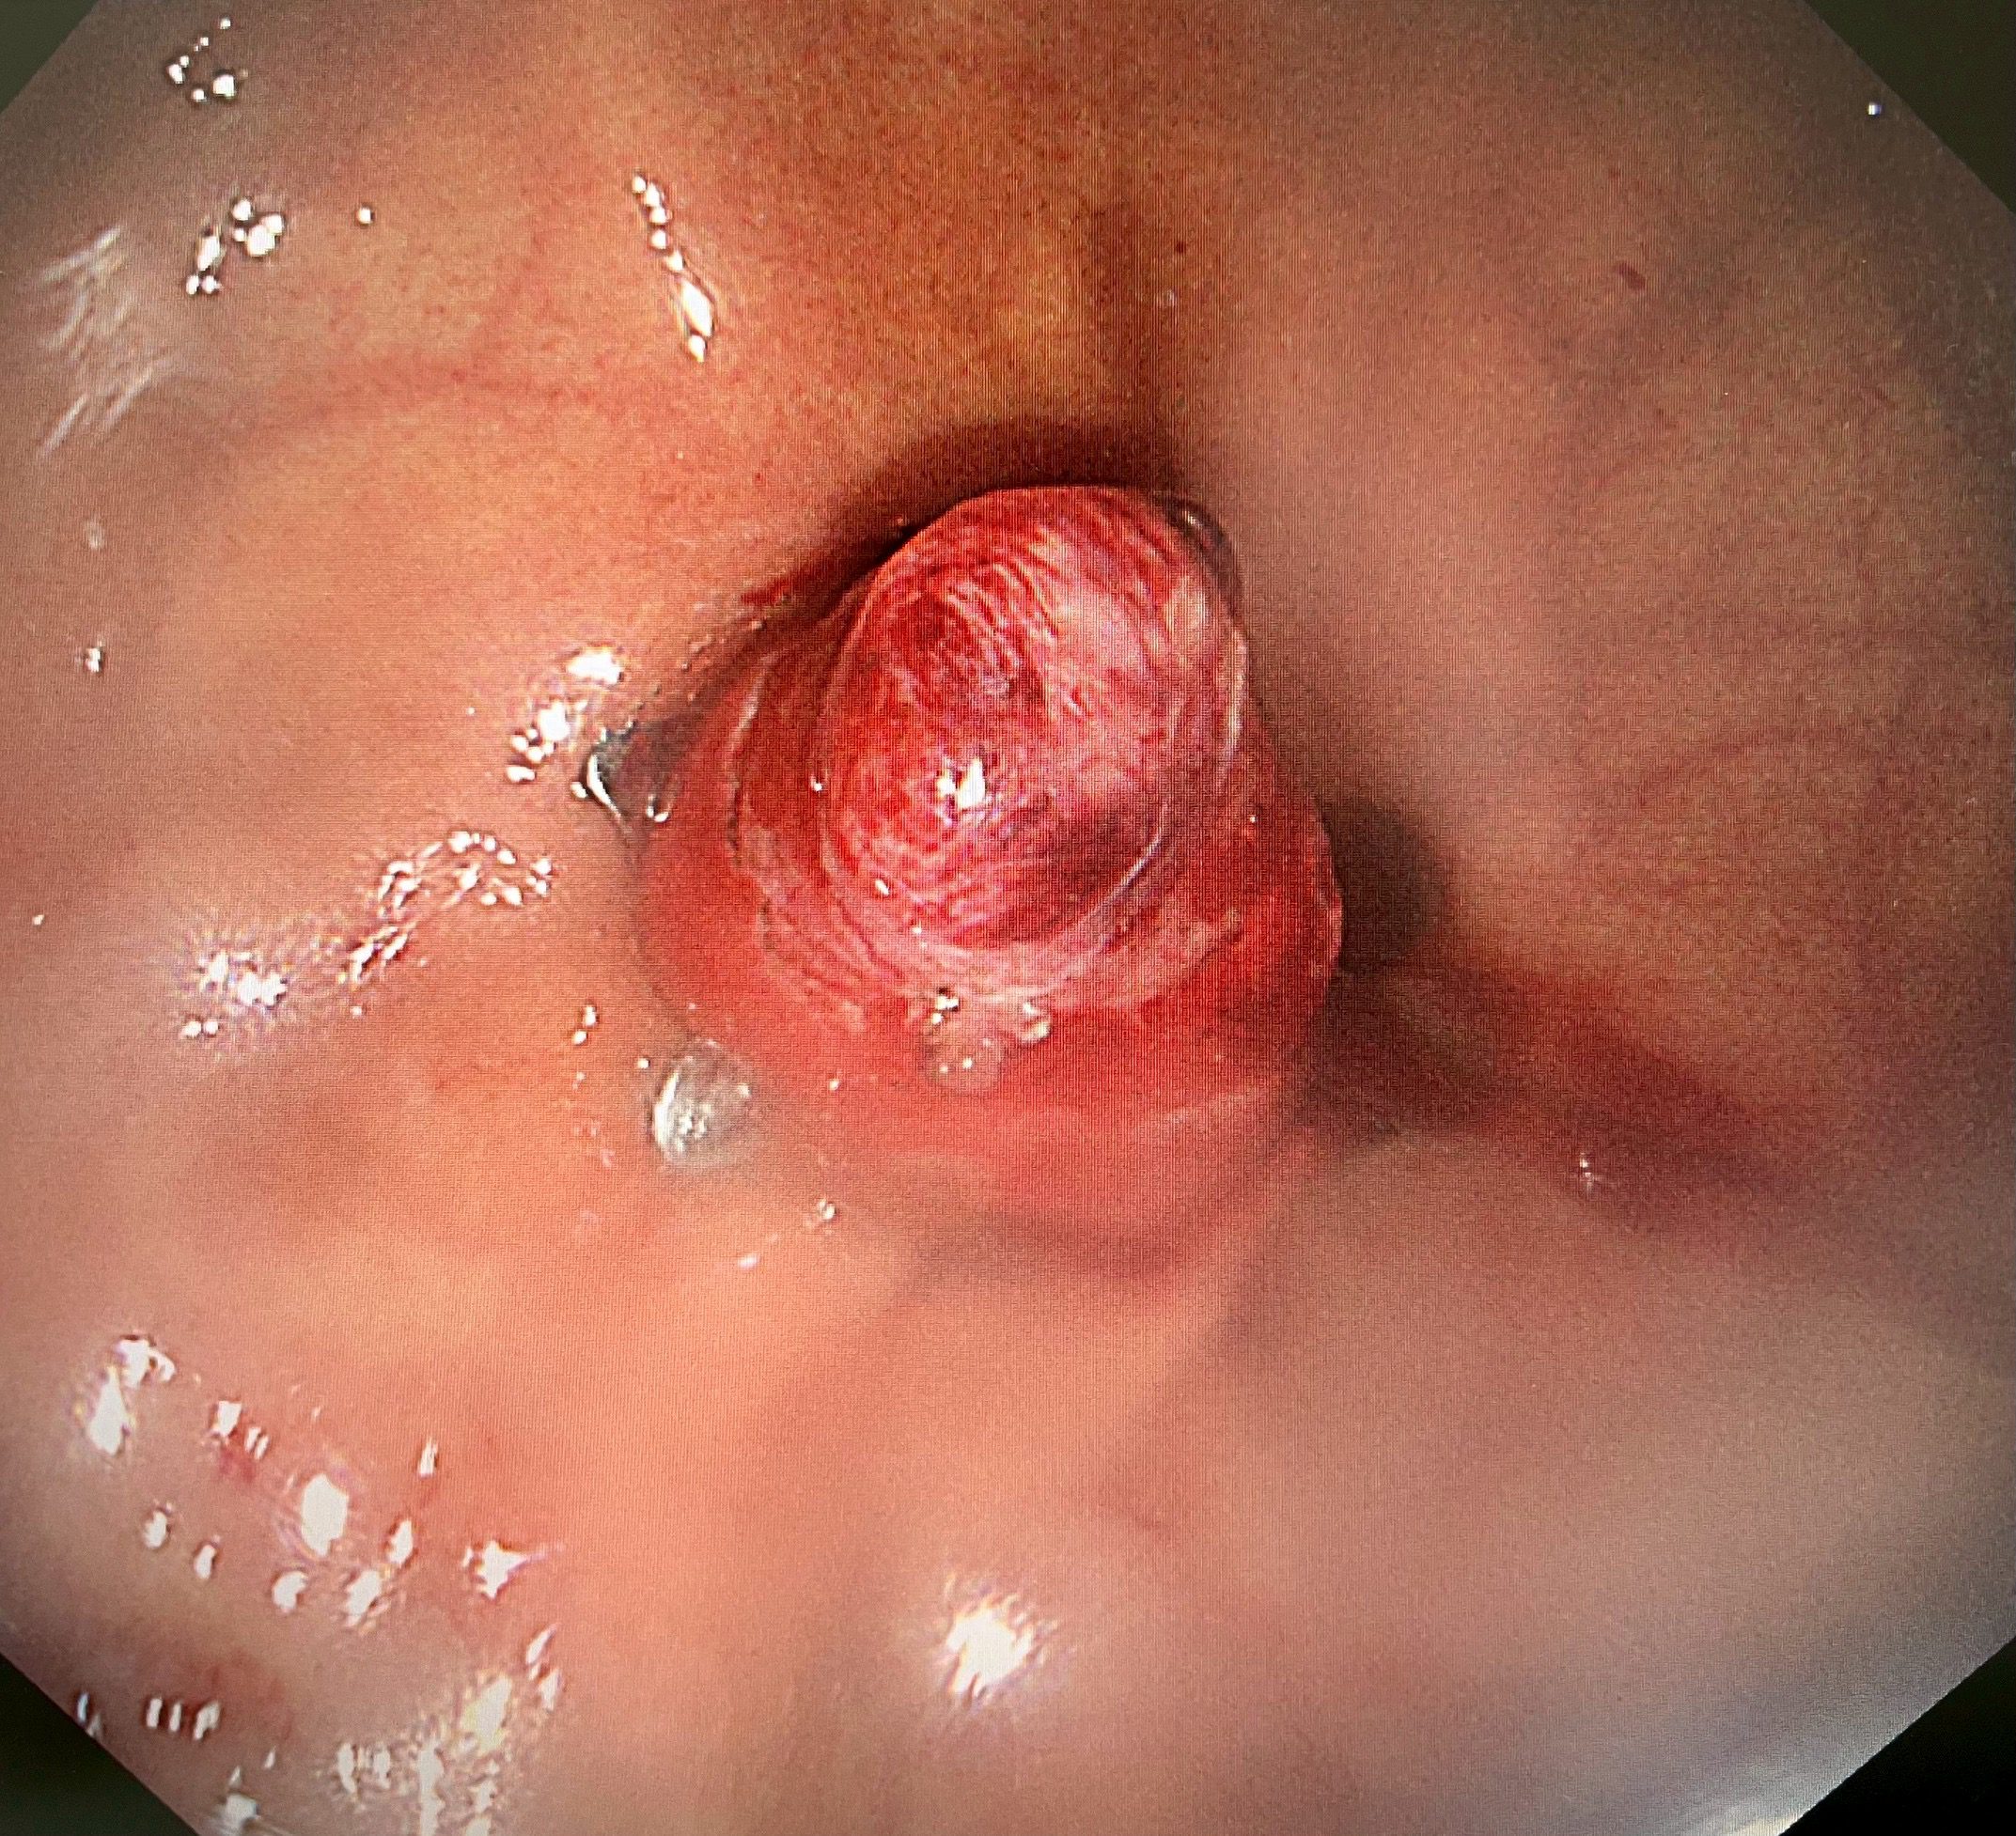

微創手術新突破:25分鐘完成全層切除(Endoscopic Full Thickeness Resection,EFTR)

陳鴻運醫師採用新式的「內視鏡全層切除術」(EFTR)配合「pad lock clip closure device」閉合器械,僅花了25分鐘就成功將腫瘤完整切除(En Bloc resection)。這種技術能夠完整切除胃壁全層的病變,同時使用特殊夾具迅速閉合創口,避免胃內容物外漏導致腹膜炎等併發症。

「手術過程非常順利」,陳鴻運醫師描述:「我們透過內視鏡直視下將腫瘤完整切除,並立即使用pad lock clip閉合裝置關閉胃壁缺損。患者麻醉醒後完全沒有任何不適,沒有腹痛、腹脹等症狀。」